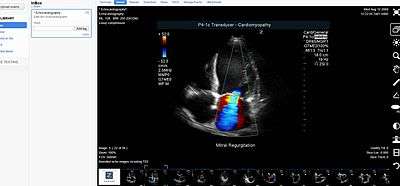

Medical Image Sharing is a term for the electronic exchange of medical images between hospitals, physicians and patients. Rather than using traditional media, such as a CD or DVD, and either shipping it out or having patients carry it with them, technology now allows for the sharing of these images using the cloud. The primary format for images is DICOM (Digital Imaging and Communications in Medicine). Typically, non-image data such as reports may be attached in standard formats like PDF (Portable Document Format) during the sending process. Additionally, there are standards in the industry, such as IHE Cross Enterprise Document Sharing for Imaging (XDS-I), for managing the sharing of documents between healthcare enterprises. A typical architecture involved in setup is a locally installed server, which sits behind the firewall, allowing secure transmissions with outside facilities. In 2009, the Radiological Society of North America launched the "Image Share" project, with the goal of giving patients control of their imaging histories (reports and images) by allowing them to manage these records as they would online banking or shopping.[1]

- Picture archiving and communication system (PACS) - A medical imaging technology that provides economical storage of, and convenient access to, images from multiple modalities within a facility.